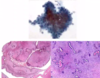

Describe what this image shows. What do the purple stains/pink area/blue arrow show?

terminal duct lobular unit (TDLU)

- from nipple → branches → end in TDLU

- consist of SNIs and ducts

purple = glandular tissue

pink = stroma

large pink circle = duct with acini around duct

blue arrows = myoepithelial cells - helps pump milk. epithelial (luminal) cells are on inside of myoepithelial cells